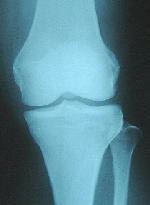

正常な膝、変形性膝関節症、人工関節のレントゲン写真をご紹介します。